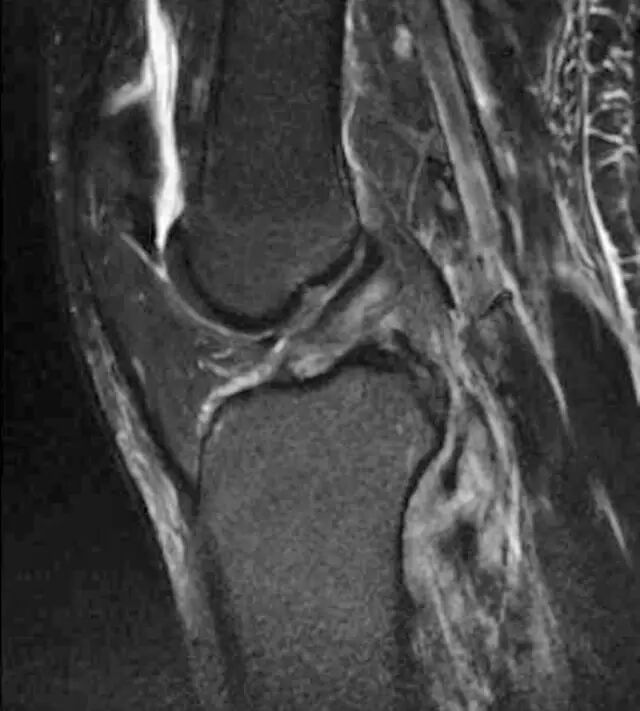

图7A、B、C-两名患者具有撕脱性骨折信号潜在损伤。A,32岁的踝关节受伤的男子在秋天受伤。侧面X线片显示最小移位后踝骨折(箭头),指示踝关节融合的破裂。B,30岁的男子汽车与行人碰撞后。冠状(B)和矢状(C)STIR MR图像显示在外侧胫骨坪(箭头,B)和全厚度前十字韧带撕裂处的急性Segond骨折。

另一个典型的例子是Segond断裂(图7B和7C)。这种骨折发生在外侧胫骨,似乎是侧膝关节囊撕裂的结果。已有许多研究显示Segond骨折与主要软组织损伤(包括前交叉韧带和半月板)的高度关联[29,30]。撕裂性骨折的其他频繁部位包括内侧和外侧股骨髁,胫骨的中间隆起,腓骨头,踝的内侧和外侧踝,远侧胫骨的前外侧边缘,距骨的背侧颈, 跟骨的前部过程,以及第二和第五跖骨的基部。当存在小的脉冲断裂片段时,放射科医生应确定通过哪种软组织结构附着于骨片段来考虑潜在的软组织分支。